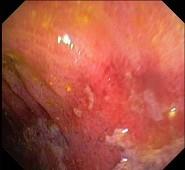

男性,68岁,腹痛1周,便血1天,既往有糖尿病和高血压病史。查体BP170/80mmHg,腹软,左下腹有压痛,无明显反跳痛,肠鸣音减弱。肠镜检查图片如下,...

问题 男性,68岁,腹痛1周,便血1天,既往有糖尿病和高血压病史。查体BP170/80mmHg,腹软,左下腹有压痛,无明显反跳痛,肠鸣音减弱。肠镜检查图片如下,最可能的诊断是 ( )

选项 A、Crohn病 B、肠结核 C、大肠癌 D、溃疡性结肠炎 E、缺血性结肠炎

答案 E